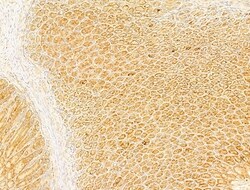

| Immunocytochemistry, Immunohistochemistry (Paraffin), Western Blot | |